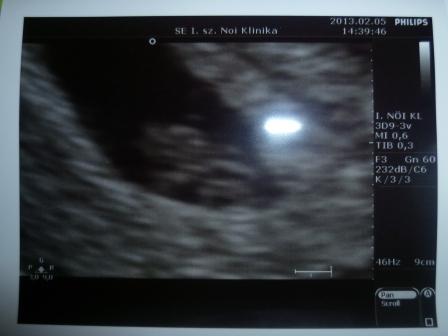

Yza, teljesen igazad van, ezek után én sem bíznék meg ebben a dokiban. Magára bármit is adó szakember ilyet nem enged meg magának! Nekem is hasonló méretû volt amúgy a bogyókám utoljára (12.8 mm), és arra is 7+3-at mondott a doki. Ez múlt pénteken volt. A mensi szerint nekem is több lenne, de már az elejétõl mondta, hogy elég késõn fogant. Pénteken megint megyek.

Biztos megnyugtató hallani a kis szíve dobogását! Nekem eddig sajnos az ultrahangon nem kapcsoltak rá hangot (nem tudom, hogy lehet-e egyáltalán), mindig csak megmutatták a képen, hogy vibrál.